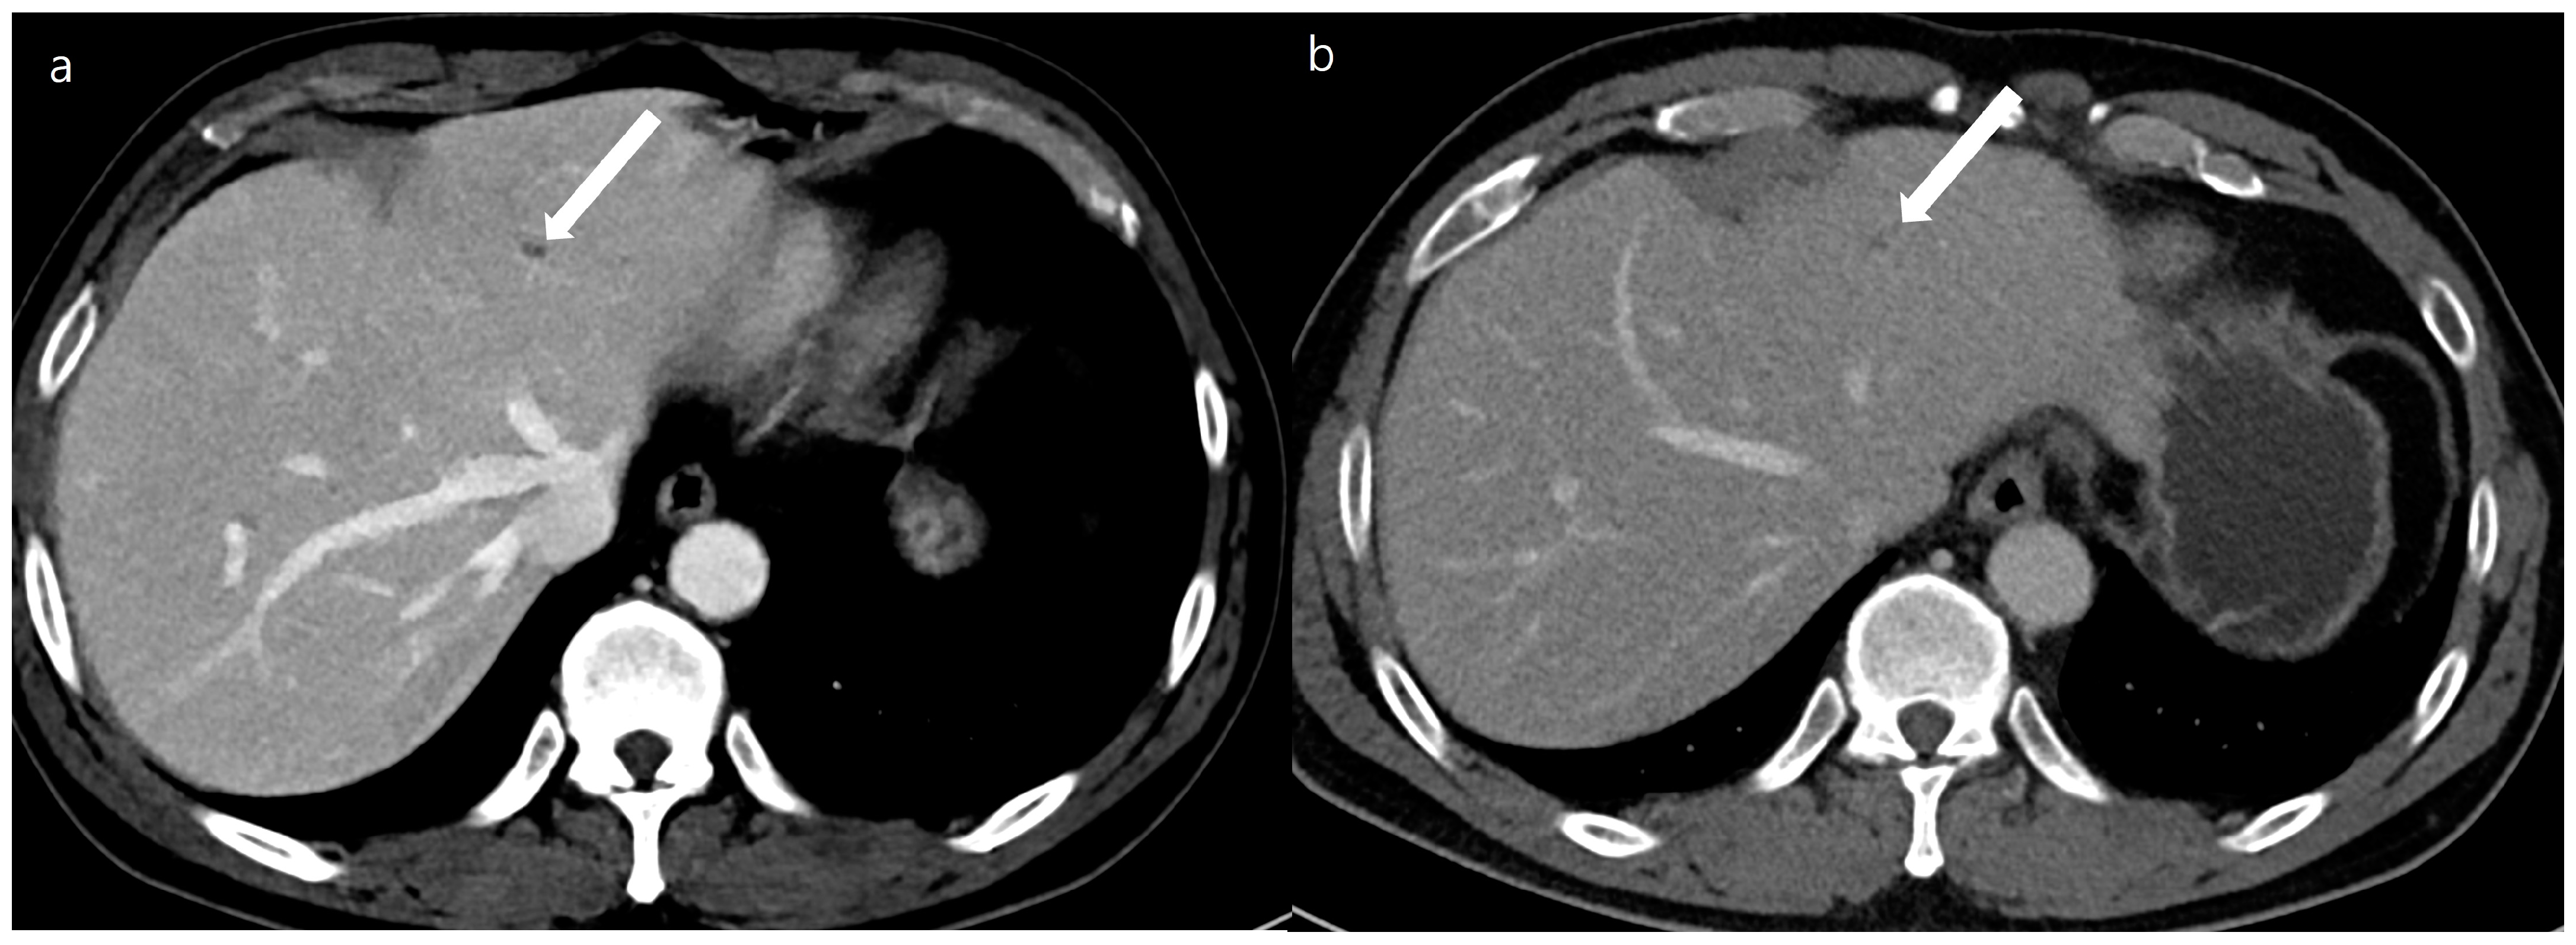

Figure 4. A 54-year-old man with a 0.4 cm sized small focal low density at segment 2 of the liver (arrows). A double low-dose CT using a deep-learning-based contrast-boosting model (a) shows better conspicuity (Reviewer 1, 4; Reviewer 2, 5) of the focal lesion (arrows) than standard-dose CT using hybrid iterative reconstruction (Reviewer 1, 2; Reviewer 2, 1) (b) at portal phase images (time interval: 11 months). Two reviewers evaluated the double low-dose CT using a deep-learning-based contrast-boosting model and standard-dose CT using hybrid iterative reconstruction. The results demonstrated no difference in overall image quality.